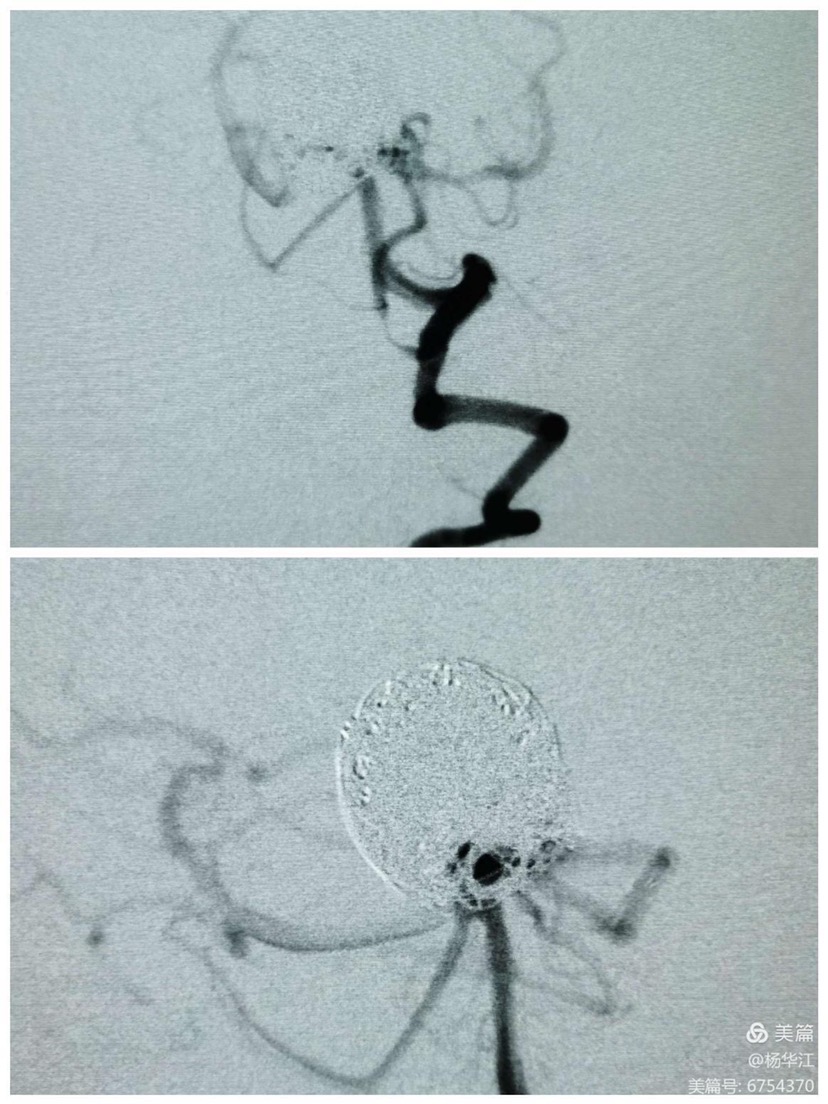

术中先行后循环造影显示:动脉瘤几乎完全不显影,各分支显影良好。这个效果还是有些出乎我们的意料的好,大概率消除了迟发性出血这个隐患。

这是我们用了10年之久西门子机器做出的3D后处理影像,还行吧,尽管稍有些失真。

Pipeline结合弹簧圈处理左侧床突上段巨大动脉瘤

动脉瘤相对窄颈,射流比较明显。

以下为常规操作,就不赘述了。

填两枚大圈后,动脉瘤下半部分已经不显影,此时见动脉瘤上半部分射流明显,直冲瘤顶。

需要继续填圈阻断射流!

填圈至此,射流被阻断,瘤顶已不显影。

DynaCT双容积显示pipeline贴壁良好。

术后患者一切如常,观察5天后无异常出院。现为第一次术后40天、第二次术后25天,电话随访患者一切正常。期待后续的临床和影像随访。